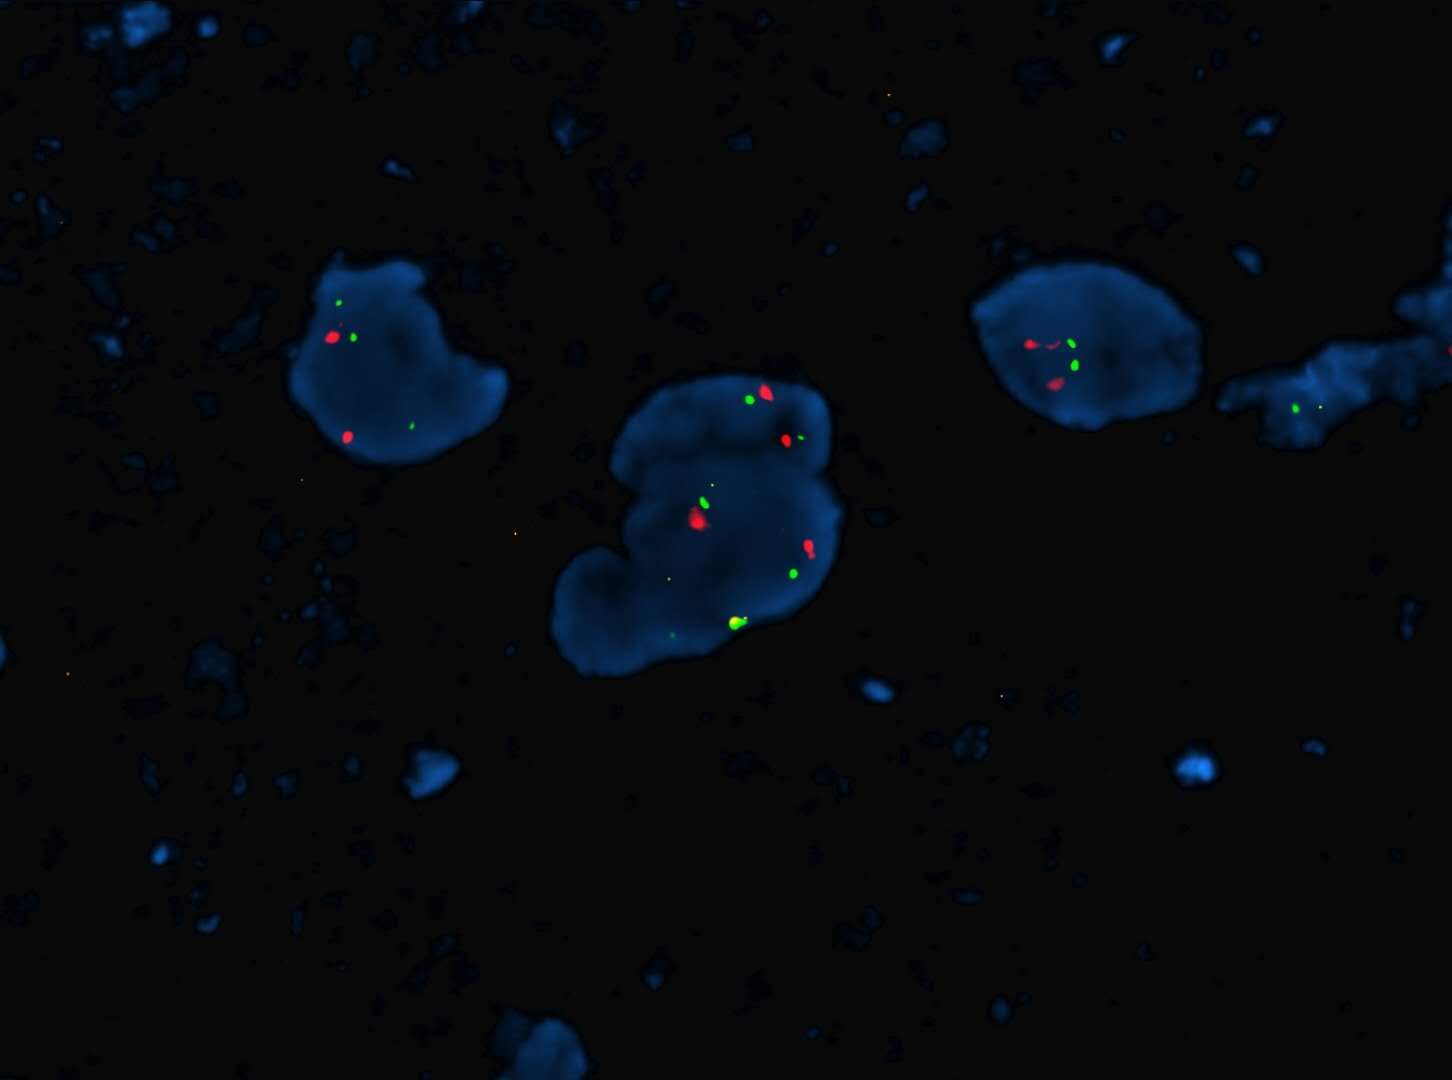

FISH 探針定製服務--成像美觀,多探針高度融合

熒光原位雜交技術(Fluorescencein situ hybridization, FISH) 是根據已知微生物不同分類級別上種群特異的DNA序列,以利用熒光標記的特異寡聚核苷酸片段作為探針,與環境基因組中DNA分子雜交,檢測該特異微生物種群的存在與豐度。

C. 多色標記,簡單直觀;